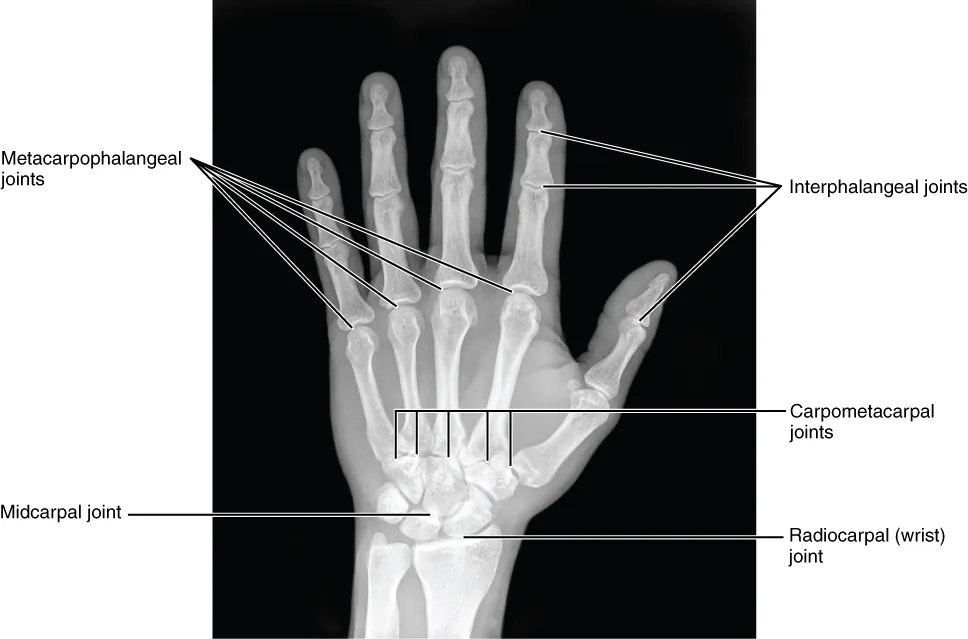

This image shows a radiograph of a human hand.

Figure 8.8 Bones of the Hand This radiograph shows the position of the bones within the hand. Note the carpal bones that form the base of the hand. (credit: modification of work by Trace Meek)

The carpal bones form the base of the hand. This can be seen in the radiograph (X-ray image) of the hand that shows the relationships of the hand bones to the skin creases of the hand (see Figure 8.8). Within the carpal bones, the four proximal bones are united to each other by ligaments to form a unit. Only three of these bones, the scaphoid, lunate, and triquetrum, contribute to the radiocarpal joint. The scaphoid and lunate bones articulate directly with the distal end of the radius, whereas the triquetrum bone articulates with a fibrocartilaginous pad that spans the radius and styloid process of the ulna. The distal end of the ulna thus does not directly articulate with any of the carpal bones.

The four distal carpal bones are also held together as a group by ligaments. The proximal and distal rows of carpal bones articulate with each other to form the midcarpal joint (see Figure 8.8). Together, the radiocarpal and midcarpal joints are responsible for all movements of the hand at the wrist. The distal carpal bones also articulate with the metacarpal bones of the hand.

The palm of the hand contains five elongated metacarpal bones. These bones lie between the carpal bones of the wrist and the bones of the fingers and thumb (see Figure 8.7). The proximal end of each metacarpal bone articulates with one of the distal carpal bones. Each of these articulations is a carpometacarpal joint (see Figure 8.8). The expanded distal end of each metacarpal bone articulates at the metacarpophalangeal joint with the proximal phalanx bone of the thumb or one of the fingers. The distal end also forms the knuckles of the hand, at the base of the fingers. The metacarpal bones are numbered 1–5, beginning at the thumb.

The fingers and thumb contain 14 bones, each of which is called a phalanx bone (plural = phalanges), named after the ancient Greek phalanx (a rectangular block of soldiers). The thumb (pollex) is digit number 1 and has two phalanges, a proximal phalanx, and a distal phalanx bone (see Figure 8.7). Digits 2 (index finger) through 5 (little finger) have three phalanges each, called the proximal, middle, and distal phalanx bones. An interphalangeal joint is one of the articulations between adjacent phalanges of the digits (see Figure 8.8).